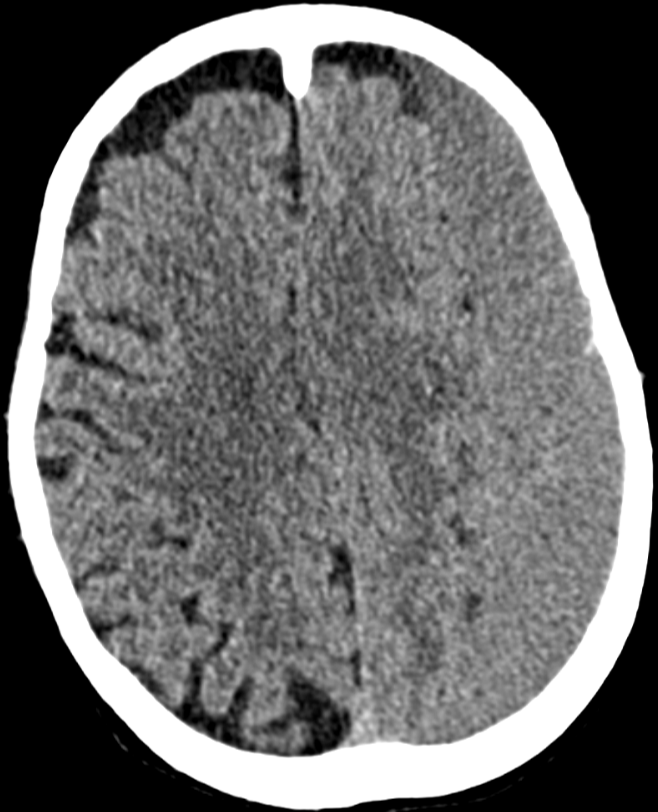

3. Subdural haematoma